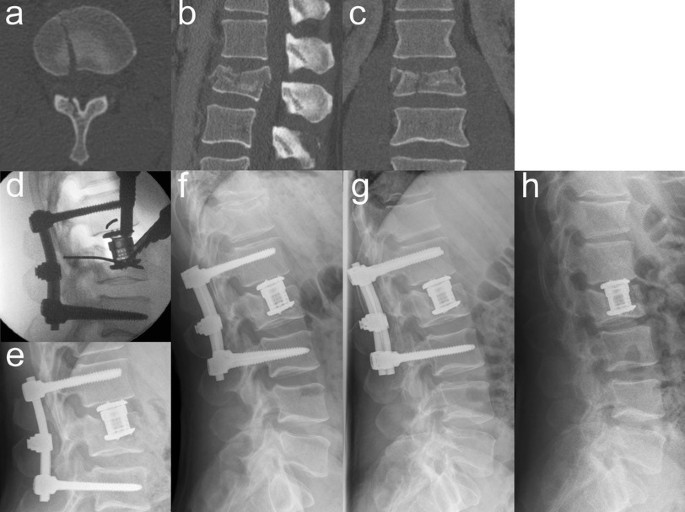

VBRD subsidence was observed in five patients (Table 4). In three of these patients, the VBRD subsided through the inferior endplate of the fractured vertebra and into the adjacent intervertebral disc (Figs. 2, 3). In the other two patients, the VBRD subsided into the cancellous bone until the inferior endplate was reached (Fig. 4). VBDR subsidence through the inferior endplate was already apparent intraoperatively (one case) or on first radiograph after postoperative mobilization (two cases), whereas VBDR subsidence into the cancellous bone occurred later but became evident on follow-up radiographs within 3 months post surgery. When comparing patients with and without VBRD subsidence after monosegmental ACR, however, differences in monosegmental (4.0 ± 2.6° vs. 2.2 ± 2.7°, P = 0.22) and bisegmental (5.8 ± 3.0° vs. 4.9 ± 4.0°, P = 0.67) loss of correction did not reach significance.

Illustrative case of VBRD subsidence into the cancellous bone after monosegmental ACR. Axial (a), sagittal (b) and coronal (c) CT reconstructions showing a burst-split fracture of L2 and one single split fracture line at the inferior endplate of the fractured vertebra (a). Intraoperative lateral radiograph (d) demonstrating that the VBRD was placed too far cranially to the inferior endplate of the fractured vertebra and anchored into the weak cancellous bone. Postoperative lateral radiographs at 1 month (e), 3 months (f), 6 months (g) and 13 months (h after implant removal): VBDR subsidence occurred between 1 and 3 months after surgery and is clearly evident at 3-month follow-up (f)